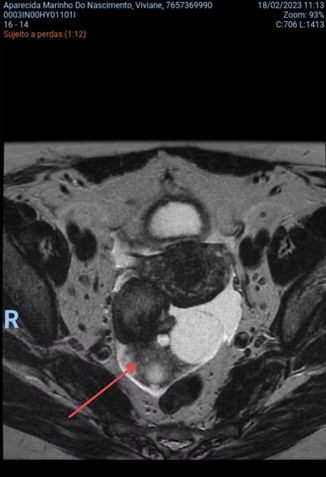

A 50-year-old female patient, asymptomatic, in a routine gynecological medical consultation, was requested to perform a transvaginal ultrasonography, which revealed an enlarged right ovary, showing regular contours and heterogeneous echotexture due to the presence of a nodular, heterogeneous, predominantly echogenic image, with areas of posterior acoustic shadow measuring approximately 3.2 x 3.1 cm. Dermoid cyst was questioned by the ultrasonographer and recommended further investigation with MRI. The patient underwent the suggested examination within a few days and the right ovary was found to be enlarged, displaced posteriorly, measuring approximately 7 x 5.6 x 2.8 cm, associated with the presence of simple cystic formations measuring up to 3.2 cm and one with thick content measuring 2.1 cm (Figure 1 and 2). It is also noted the presence of two hypovascular nodular formations in between, with heterogeneous signal, in close proximity to the serosa of the right lateral uterine body wall, measuring 4.5 x 3.1 cm.

Figure 1 Right adnexal mass axial plane in MRI demonstrated by red arrow.